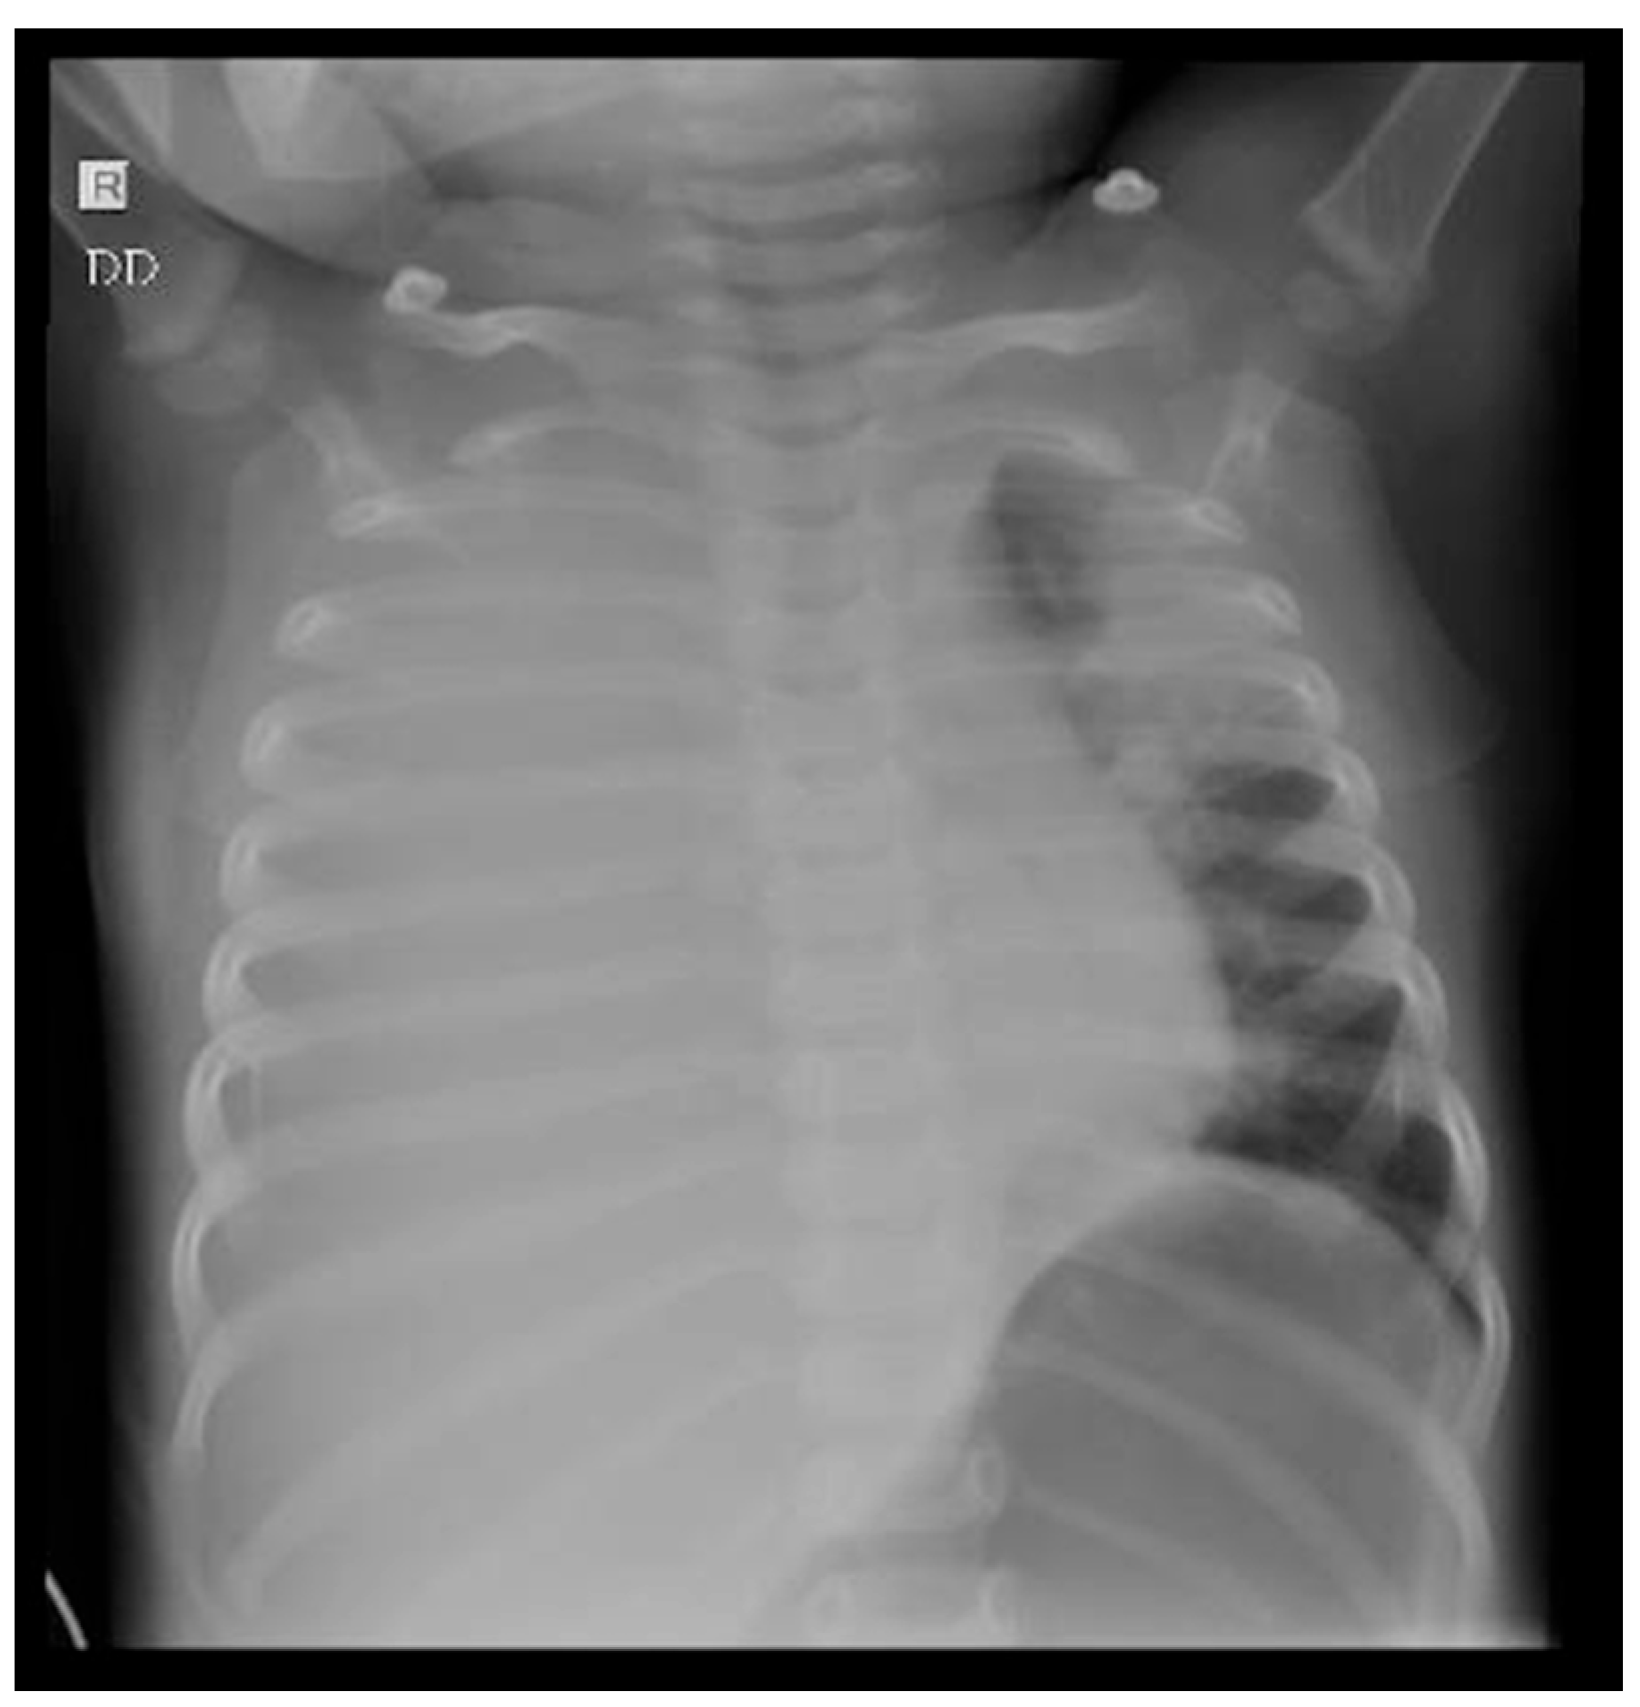

3.1. Case 1

3.2. Case 2